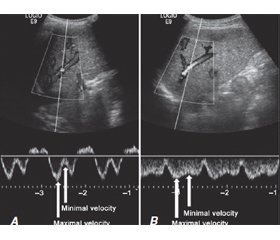

Багато дослідників і клініцистів вважають значення градієнта печінкового венозного тиску (ГПВТ) суттєвим прогностичним фактором у пацієнтів із хронічними захворюваннями печінки. Значення ГПВТ ≥ 10 мм рт.ст. визначають наявність клінічно значущої портальної гіпертензії (КЗПГ), основного предиктора ризику варикозної кровотечі, декомпенсації печінки та смертності. Однак вимірювання ГПВТ є інвазійним і вимагає значного досвіду, тому його рутинне використання за межами центрів третього рівня або клінічних випробувань обмежене. Клінічно значущу портальну гіпертензію також можна визначити за допомогою неінвазійних методів, як-от ультрасонографія, еластографія, магнітно-резонансна томографія та показники, отримані на підставі лабораторних параметрів. Наш огляд має на меті представити доцільність і застосовність ГВПТ у сучасній клінічній практиці у хворих на цироз печінки, включно з інвазійними та неінвазійними методами, на підставі літературних джерел з бази MedLine.

Many researchers and clinicians have taken the value of hepatic venous pressure gradient (HVPG) as an essential prognostic factor in subjects with chronic liver diseases. HVPG ≥ 10 mmHg indicates the presence of clinically significant portal hypertension, the main predictor of the risk of variceal bleeding, hepatic decompensation, and mortality. However, HVPG measurement is invasive and requires high expertise, so its routine use outside tertiary care centers or clinical trials is limited. Clinically significant portal hypertension also might be detected using non-invasive options such as ultrasonography, elastography, magnetic resonance imaging, and indices derived from laboratory parameters. Our review aims to present the feasibility and applicability of HVPG in modern clinical practice in patients with liver cirrhosis, including invasive and non-invasive methods, based on literary sources from the MEDLINE database.

- Kim G., Cho Y.Z., Baik S.K., Kim M.Y., et al. The accuracy of ultrasonography for the evaluation of portal hypertension in patients with cirrhosis: a systematic review. Korean J. Radiol. 2015. Vol. 16. P. 314-324.

- Maruyama H., Yokosuka O. Ultrasonography for Noninvasive Assessment of Portal Hypertension. Gut Liver. 2017. Vol. 11. P. 464-473.